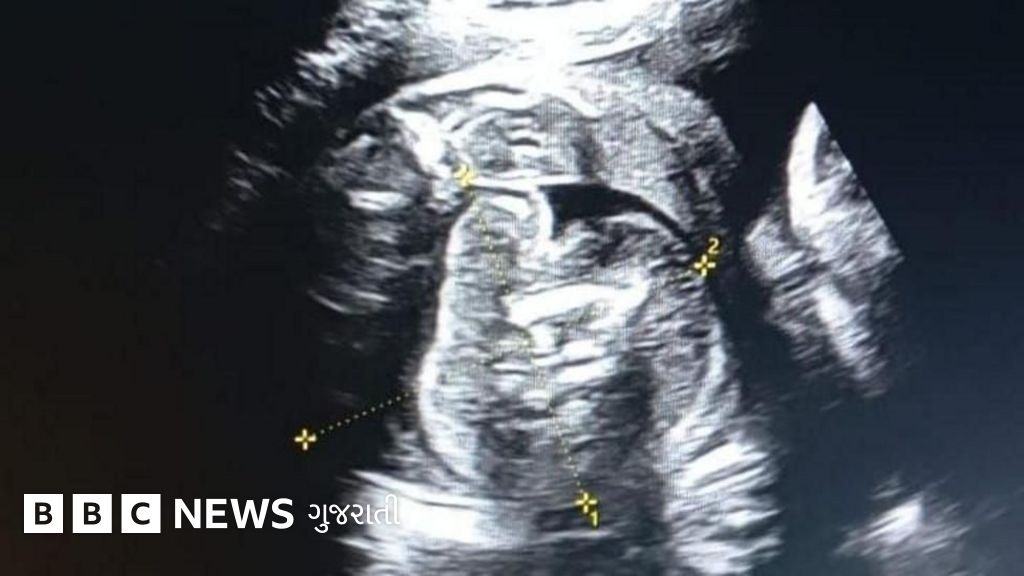

મહારાષ્ટ્રના બુલઢાણા જિલ્લામાં એક મહિલાના પેટમાં બાળક અને તેના પેટમાં પણ એક બાળક જોવા મળ્યું.

બુલઢાણા જિલ્લાની એક ગર્ભવતી મહિલા સોનોગ્રાફી માટે સરકારી હૉસ્પિટલમાં ગઈ હતી, ત્યારે આ ઘટના ઉજાગર થઈ.

સોનોગ્રાફી કર્યા પછી સંબંધિત મહિલાના પેટમાં બાળક હતું અને બાળકના પેટમાં પણ બાળક જોવા મળ્યું.

બુલઢાણા જિલ્લાની 32 વર્ષીય એક મહિલા ગર્ભાવસ્થાના આઠમા મહિને સોનોગ્રાફી માટે એક સરકારી હૉસ્પિટલમાં આવી હતી.

તેની તપાસ કર્યા પછી ખબર પડી કે, મહિલાના પેટમાં જે ભ્રૂણ છે તેમાં પણ એક ભ્રૂણ દેખાય છે.

એટલે સુધી કે, જ્યારે ડૉક્ટરો અને નિષ્ણાતોની ટીમે ફરી વખત સોનોગ્રાફી કરી ત્યારે બાળકના પેટમાં ગર્ભ સ્પષ્ટ દેખાતો હતો.